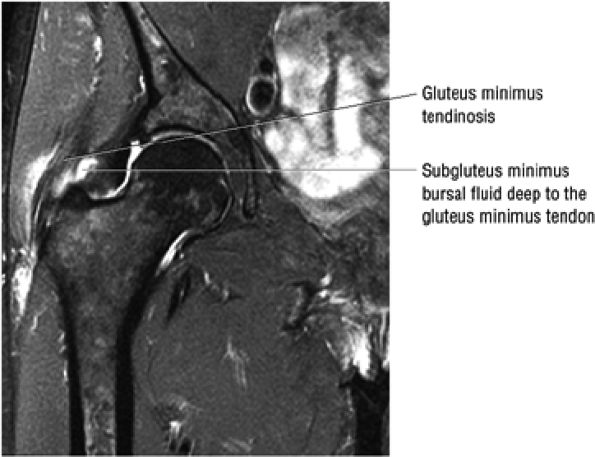

or secondary to communication with the hip joint. Trochanteric bursitis suspected on coronal images is confirmed on axial images.